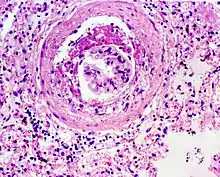

Glomerulosclerosis is the hardening of the glomeruli in the kidney. It is a general term to describe scarring of the kidneys' tiny blood vessels, the glomeruli, the functional units in the kidney that filter urea from the blood.

Proteinuria (large amounts of protein in the urine) is one of the signs of glomerulosclerosis. Scarring disturbs the filtering process of the kidneys and allows protein to leak from the blood into the urine. However, glomerulosclerosis is one of many causes of proteinuria. A kidney biopsy (the removal of a tiny part of the kidney with a needle) may be necessary to determine whether a patient has glomerulosclerosis or another kidney problem. About 15 percent of people with proteinuria turn out to have glomerulosclerosis.